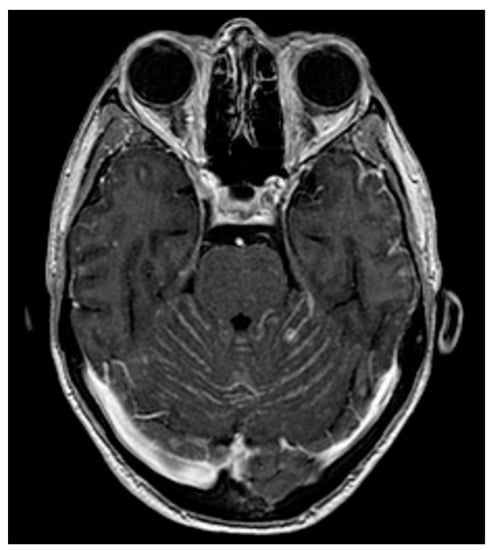

4.2. Neuroimaging Assessment